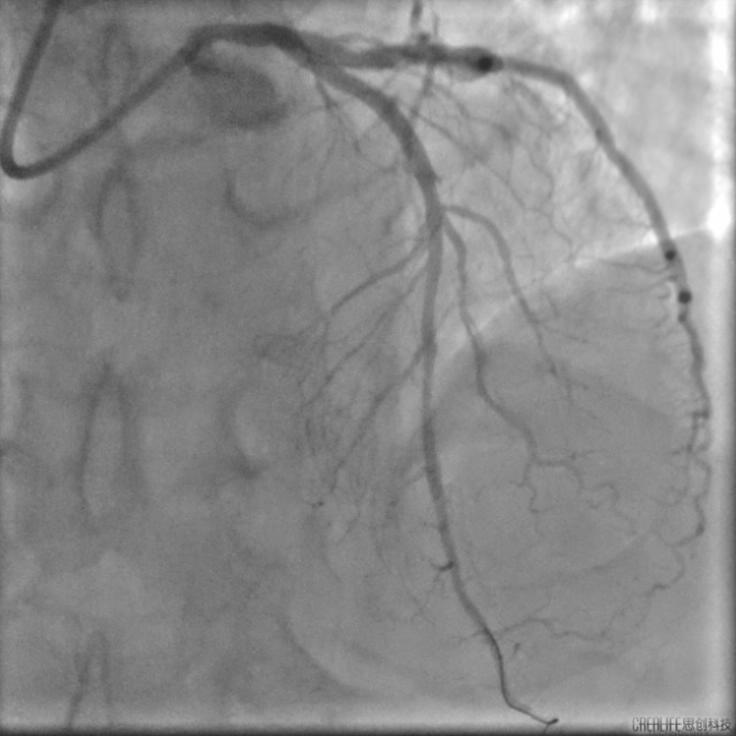

胡洵教授应用TRUEVISION® & VivoHeart®系统指导完成了一例前降支弥漫病变的PCI治疗。该名患者前降支病变长度超过60mm,传统IVUS导管回撤耗时超过1分钟,使用TRUEVISION® & VivoHeart®系统则仅用时7秒即完成了整个病变的评估。胡洵教授指出国产新型IVUS导管术中高速回撤的优秀表现,不仅给手术医生及患者节省了宝贵的手术时间,而且更为重要的是可以有效减少患者在IVUS检查过程中可能引发的心肌缺血风险。

术后